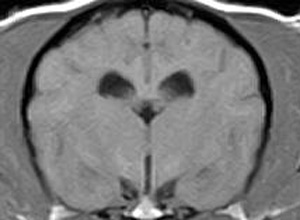

けいれん発作が出るワンちゃんが来院されました。MRI検査では脳に構造上の異常を認めず、脳脊髄液検査でも異常を認めず、特発性てんかんとの診断でお薬での治療となりました。発作は現在のところ、お薬で良好にコントロールされています。